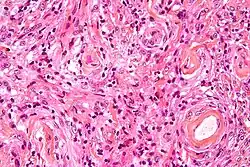

Pathophysiology

- A woven architectural pattern

- Psammoma bodies (spheroid calcifications)

- Syncytial cells (having indistinct cell membranes) with eosinophilic (pink) cytoplasms

- Round uniform nuclei

- Whorls (concentric cell arrangements)[16]

Histologically, meningioma cells are relatively uniform, with a tendency to encircle one another, forming whorls and psammoma bodies (laminated calcific concretions).[19] As such, they also have a tendency to calcify and are highly vascularized.

- ^ Image by Mikael Häggström, MD. Reference for typical findings: Chunyu Cai, M.D., Ph.D. "Meningioma". Pathology Outlines.